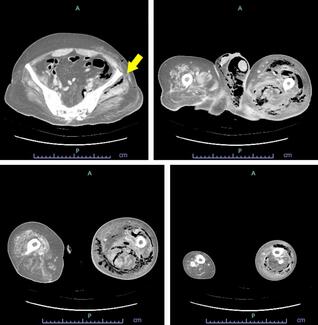

A 39-year-old male with refractory AED secondary to a crush injury in February 2019 presented. At the time of injury, he underwent pelvic reconstruction and colostomy creation with reversal. The patient initially presented to an outside hospital after his injury and initial evaluation prior to seeking care with our plastic surgery team for the AED in April 2021. His operation was performed in July 2021, after his colostomy reversal was completed and he had recovered from that operation. Other than being unable to achieve an erection, the patient denied other urologic symptoms. Patient was a former smoker with 34-pack-year history. Urologic workup included a pelvic angiogram showing complete occlusion of the anterior division of the left internal iliac artery and the left internal pudendal artery without significant collateral reconstitution. Our plan involved revascularization of the penis utilizing the right DIEA with anastomosis to DPV in conjunction with urology. CT angiogram of the abdomen and pelvis was performed to assess the donor vessels preoperatively.

This case is a 32-year-old male with refractory AED secondary to a crush injury in June 2019. He initially presented to an outside hospital before meeting with our plastic surgery team in January 2022, with his operation performed in March 2022. Following his original trauma, he required open suprapubic tube placement and multiple cystoscopies for a urethral injury as well as open fixation of a pelvic fracture. Recovery was complicated by a membranous urethral stricture requiring a posterior urethroplasty in November 2019. At the time of our assessment, the patient was voiding spontaneously but was unable to achieve an erection. The patient denied a history of smoking. Workup with urology included a pelvic angiogram showing patent bilateral iliac arteries and bilateral inferior epigastric arteries but complete occlusion of the distal left internal pudendal artery with no filling of the left dorsal or cavernosal penile artery branches as well as complete occlusion of the distal right penile artery. Our plan was for circumcision and revascularization of the penis utilizing the right DIEA with anastomosis to DPV in conjunction with urology. Computed tomography angiogram of the abdomen and pelvis was performed to assess the donor vessels preoperatively.

Immediate postoperative course was uneventful, and patient was discharged on postoperative day (POD) 1. At the time of discharge, Doppler signals were triphasic, the shaft and glans of the penis were well perfused, and there was expected postoperative shaft edema. During the patient's follow-up appointments with urology on POD5 and POD12, despite penile edema there was no documented concern for urinary retention at that time. His postoperative course was complicated by urinary retention on POD 22 requiring Foley placement, and development of a pelvic seroma 1 month following operation requiring interventional radiology (IR) drain placement. Prolonged postoperative glans edema (Figure 1) ultimately progressed to phimosis and balantis and required a dorsal slit procedure 1 month following the index operation. By 7 months postoperatively, patient endorsed returning to 80% of normal erections with only daily 5 mg tadalafil.

The immediate postoperative course was uneventful, and patient was discharged on POD 5. Patient subsequently developed glans edema 2 months postoperatively, ultimately requiring a revision circumcision at 8 months postoperative. At 3 months postoperatively, patient was able to achieve partial erections with 5 mg tadalafil daily.

In patients with diffuse AED secondary to blunt trauma, DPV arterialization using the DIEA is preferred as no suitable local arteries may exist for reliable direct anastomoses (Figure 2). Success rates have ranged from 25% to 70%, and this broad range may be related to the subjective and multifaceted nature of satisfactory sexual function.7 Both patients in our case series demonstrated improved sexual function, with the ability to achieve erections. The first patient was able to achieve erection and penetration without the use of pharmacotherapy, while the second patient was able to achieve erection with the use of minimal pharmacotherapy.

The most common risk of this procedure is glans hyperemia, which both our patients experienced postoperatively (Figure 1). Rates of hyperemia range from 7% to 22%, and severe cases can result in urethral compression and even glans ulceration.4,7,12 Treatment of hyperemia is the ligation of the distal deep dorsal vein via the retro-coronal plexus.13 Given the high risk of hyperemia and postoperative edema, it is important to consider the patient's circumcision status. Our first patient was not circumcised and developed severe balantis secondary to edema-induced pressure ischemia of the glans. Although this was treated with a dorsal slit creation and local wound care, complications may have been prevented by performing circumcision at the time of the first operation.